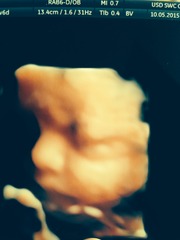

We had a 4d scan today and though I'd share them with you all!

August 2015 part 3

Ahh August! That's a crazy amount of detail - amazing!! I think it would freak me out as I'd be "that's my child" but then I'm weird. Technology is very cool!